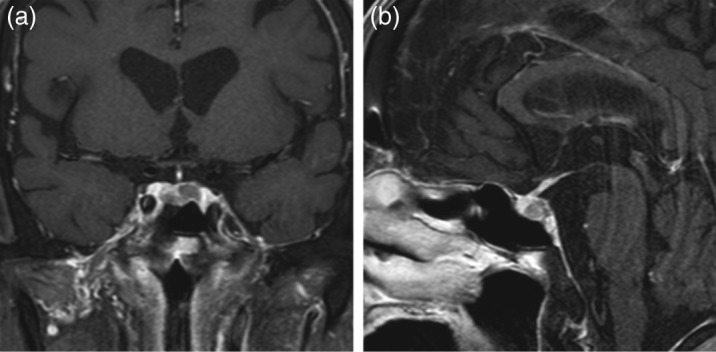

未标记:胃肠道穿孔是与类固醇治疗或高皮质醇血症相关的并发症,但在临床实践中很少在库欣病患者中观察到,只有一例被报道为首发症状。在此,我们报告一个罕见的病例库欣病,其中一个病人提出胃肠道穿孔作为症状。男,79岁,自诉下腹不适6个月。根据内分泌和胃肠检查,他被诊断为库欣病,伴有降结肠穿孔。在与胃肠外科医生会诊后,由于轻度全身性炎症和缺乏腹部保护,决定结肠穿孔可以保守观察,不需要任何口服摄入,并通过肠外给药抗生素治疗。尽管血清皮质醇水平明显升高,但由于结肠穿孔,口服药物不是一种选择。因此,患者接受鼻内腺瘤切除术以使血清皮质醇水平正常化。随后,成功进行了结肠造口术。尽管罕见,但医生应该意识到胃肠道穿孔可能与高皮质醇血症有关,特别是在老年患者中,立即诊断和治疗这种危及生命的疾病是至关重要的。如果穿孔可以保守地观察到,在剖腹手术前进行鼻内腺瘤切除术是高皮质醇症的另一种治疗选择。学习要点:迄今为止,仅报道了一例胃肠道穿孔作为库欣病的临床表现。医生应该意识到胃肠道穿孔可能与老年患者高皮质醇血症有关,因为血清皮质醇水平升高可能掩盖穿孔的临床症状。由于这种掩蔽效应,穿孔的诊断也往往延迟。虽然肠外给药依托咪酯是降低血清皮质醇升高水平的标准治疗选择,但如果没有依托咪酯治疗,剖腹手术前鼻内腺瘤切除术是另一种治疗选择。

Unlabelled: Gastrointestinal perforation is a complication associated with steroid therapy or hypercortisolism, but it is rarely observed in patients with Cushing's disease in clinical practice, and only one case has been reported as a presenting symptom. Herein, we report a rare case of Cushing's disease in which a patient presented with gastrointestinal perforation as a symptom. A 79-year-old man complained of discomfort in the lower abdomen for 6 months. Based on the endocrinological and gastroenterological examinations, he was diagnosed with Cushing's disease with a perforation of the descending colon. After consultation with a gastroenterological surgeon, it was decided that colonic perforation could be conservatively observed without any oral intake and treated with parenteral administration of antibiotics because of the mild systemic inflammation and lack of abdominal guarding. Despite the marked elevated levels of serum cortisol, oral medication was not an option because of colonic perforation. Therefore, the patient was submitted to endonasal adenomectomy to normalize the levels of serum cortisol. Subsequently, a colostomy was successfully performed. Despite its rarity, physicians should be aware that gastrointestinal perforation may be associated with hypercortisolism, especially in elderly patients, and immediate diagnosis and treatment of this life-threatening condition are essential. If a perforation can be conservatively observed, endonasal adenomectomy prior to laparotomy is an alternative treatment option for hypercortisolism.